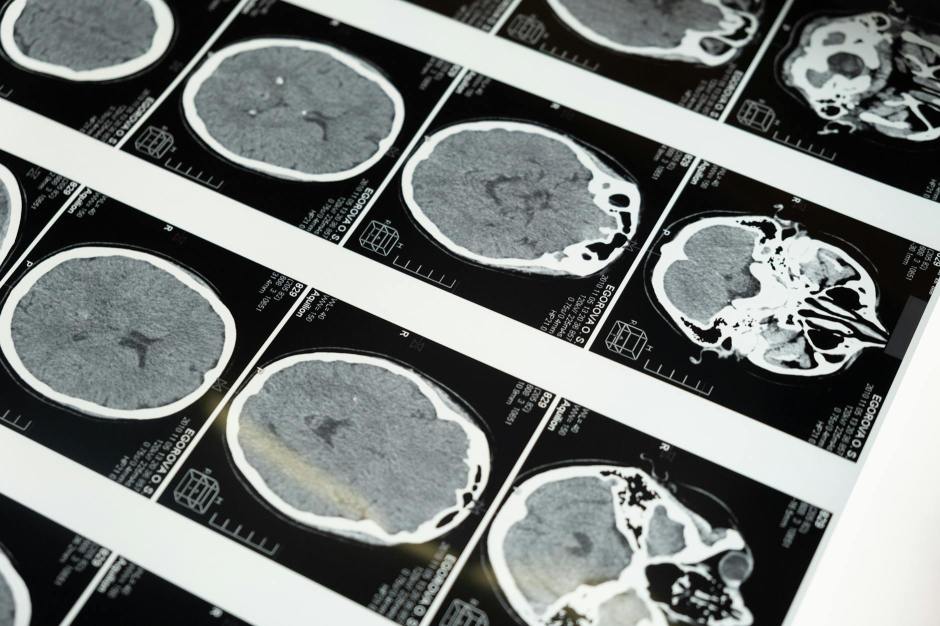

some I experienced first-hand—MRI being the latest.